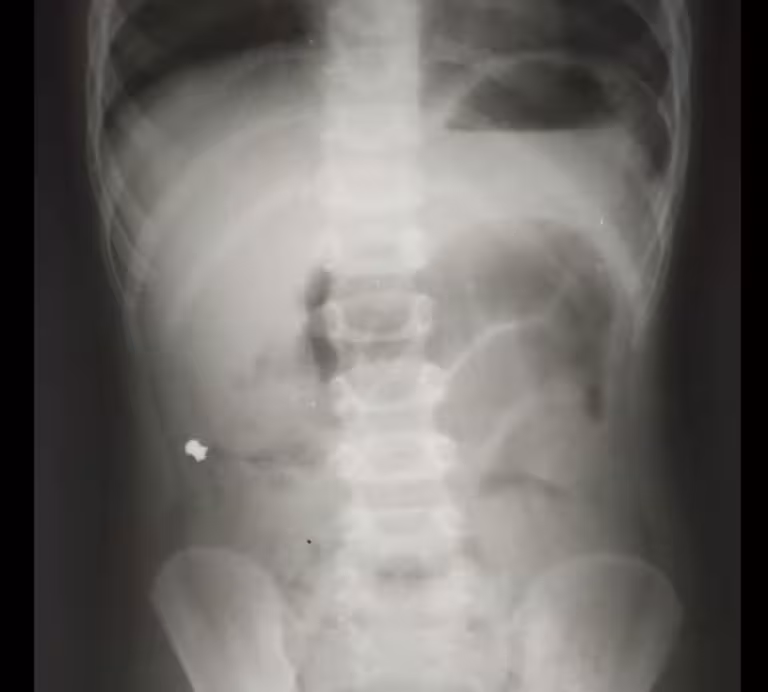

Справа, у клубовій ділянці, чітко візуалізувався сторонній предмет, але дуже дивний.

«Нашому маленькому пацієнтові від самого початку пощастило, що Кирило Володимирович відразу чітко впізнав обриси кулі від пневматичної гвинтівки. Лікар уточнив у тата хлопчика, чи могло бути, що його син проковтнув кулю. Батько пригадав, що у них вдома справді є пневматична рушниця і до неї металеві кулі. Недавно син грався коробкою з кулями. Ймовірно, випадково хлопчик проковтнув одну з них. І все б нічого, якби куля потрапила зі шлунка в кишківник і вийшла», — розповіли у лікарні.

Куля від пневматичної гвинтівка подолала незвичний шлях — замість потрапити у пряму кишку, опинилася у червоподібному відростку (апендиксі), стала причиною запального процесу у ньому і вклала дитину на операційний стіл.

«Зазвичай просвіт апендиксу перекривається каловим каменем чи навіть глистами. Слизова паростка продукує слиз у його просвіт, збільшується внутрішній тиск, порушується кровообіг, слизова апендиксу стає проникною для мікроорганізмів, які проникають всередину. Так починається запальний процес, який ми всі знаємо як апендицит. У нашому випадку коли ми видаляли апендикс, я зразу побачив, що в ньому є потовщення. Ми його видалили і вже назовні розрізали. Там справді була куля! Вона, як стороннє тіло, потрапила з кишок у апендикс і створила його обструкцію. Це і стало незвичайною причиною апендициту», — розповів дитячий хірург Кирило Лапшин.